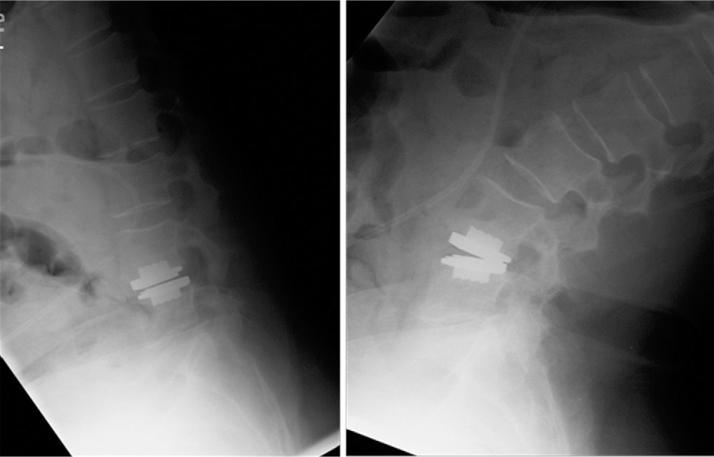

The patient was referred for genetic evaluation, which classified her with type III EDS, or hypermobility type. We presented the patient with the risks and benefits of fusion versus artificial disc replacement (ADR), particularly with regard to her EDS diagnosis of the hypermobility subtype. Given the patient's lack of extreme spinal hypermobility on examination and the absence of clear contraindications regarding ADR in type III EDS, the decision was made to proceed with ADR. There were no surgical complications, and the patient's low-back pain and radicular symptoms resolved with no evidence of implant migration or hypermobility at 1 year postoperatively.

该患者被转诊进行基因评估,结果将她归类为III型EDS,即活动过度型。我们向患者介绍了融合手术与人工椎间盘置换(ADR)的风险和益处,特别是考虑到她的EDS活动过度亚型诊断。鉴于患者检查时未出现脊柱极度活动过度,且III型EDS中ADR没有明确的禁忌证,因此决定进行ADR。手术无并发症,患者的下背痛和神经根症状得到缓解,术后1年无植入物移位或活动过度的迹象。